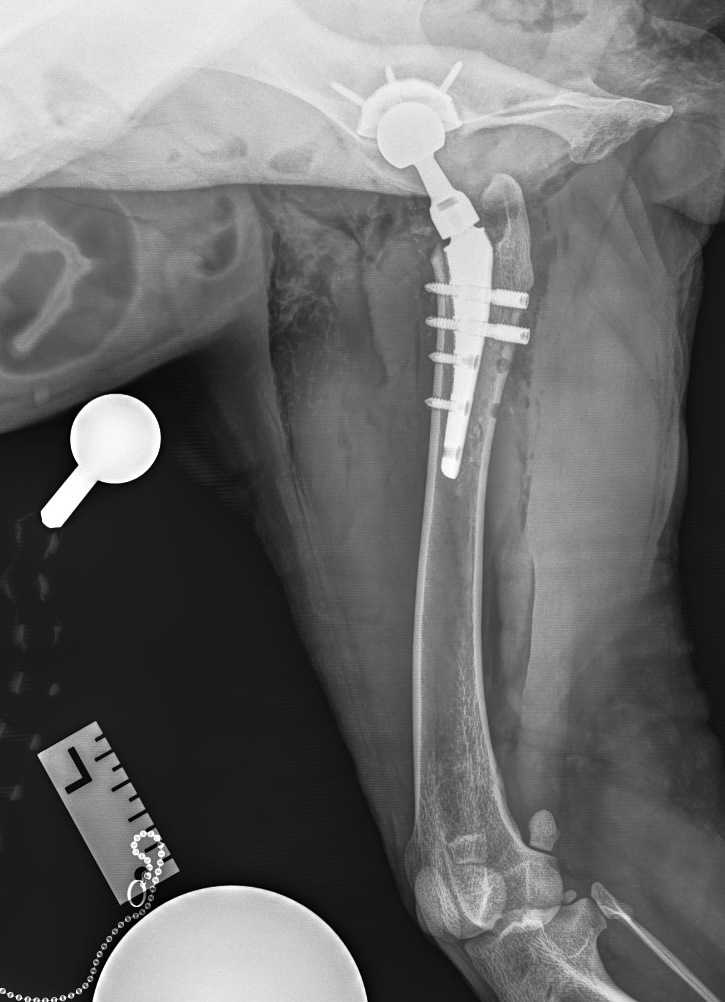

Было рекомендовано и проведено хирургическое лечение – протезирование тазобедренных суставов с интервалом между операциями в 3 месяца (фото 4).

После завершения операции выполняется серия контрольных рентгенограмм для оценки положения имплантатов (фото 4, 5).

При остеоартрите объективным доказательством наличия хронической боли может служить снижение мышечной массы больной конечности (фото 4). При односторонних состояниях это можно проверить посредством ее сравнения с мышечной массой здоровой конечности. В билатеральных случаях, например при дисплазии тазобедренных суставов, наблюдается общее снижение мышечного тонуса в мышцах тазовых конечностей6.